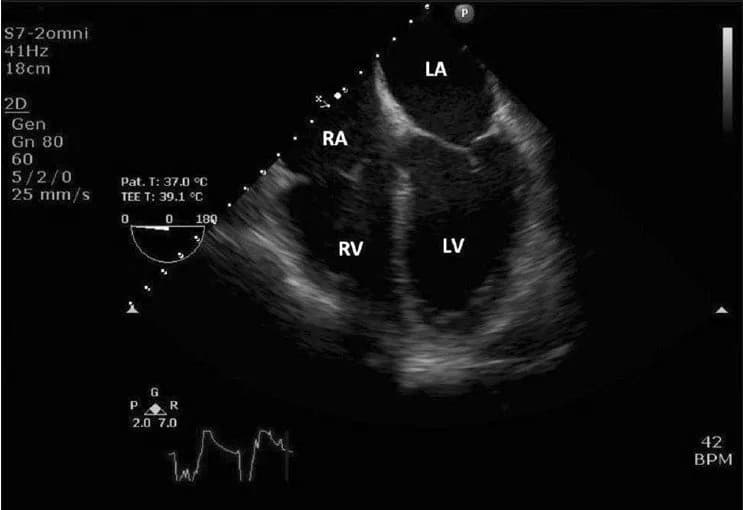

Định nghĩa: Siêu âm tim qua thực quản (TEE) là một kỹ thuật chẩn đoán hình ảnh, trong đó một đầu dò siêu âm nhỏ được gắn vào một ống mềm, sau đó đưa qua đường miệng vào thực quản của bệnh nhân. Từ vị trí này, đầu dò sẽ phát ra sóng siêu âm để tạo ra hình ảnh chi tiết về tim và các cấu trúc lân cận.

Ưu điểm: Do thực quản nằm rất gần tim, TEE cho phép thu được hình ảnh rõ nét và chi tiết hơn so với siêu âm tim qua thành ngực (TTE) thông thường. Điều này đặc biệt hữu ích trong việc đánh giá các cấu trúc nhỏ, nằm sâu hoặc bị che khuất bởi xương sườn và phổi.